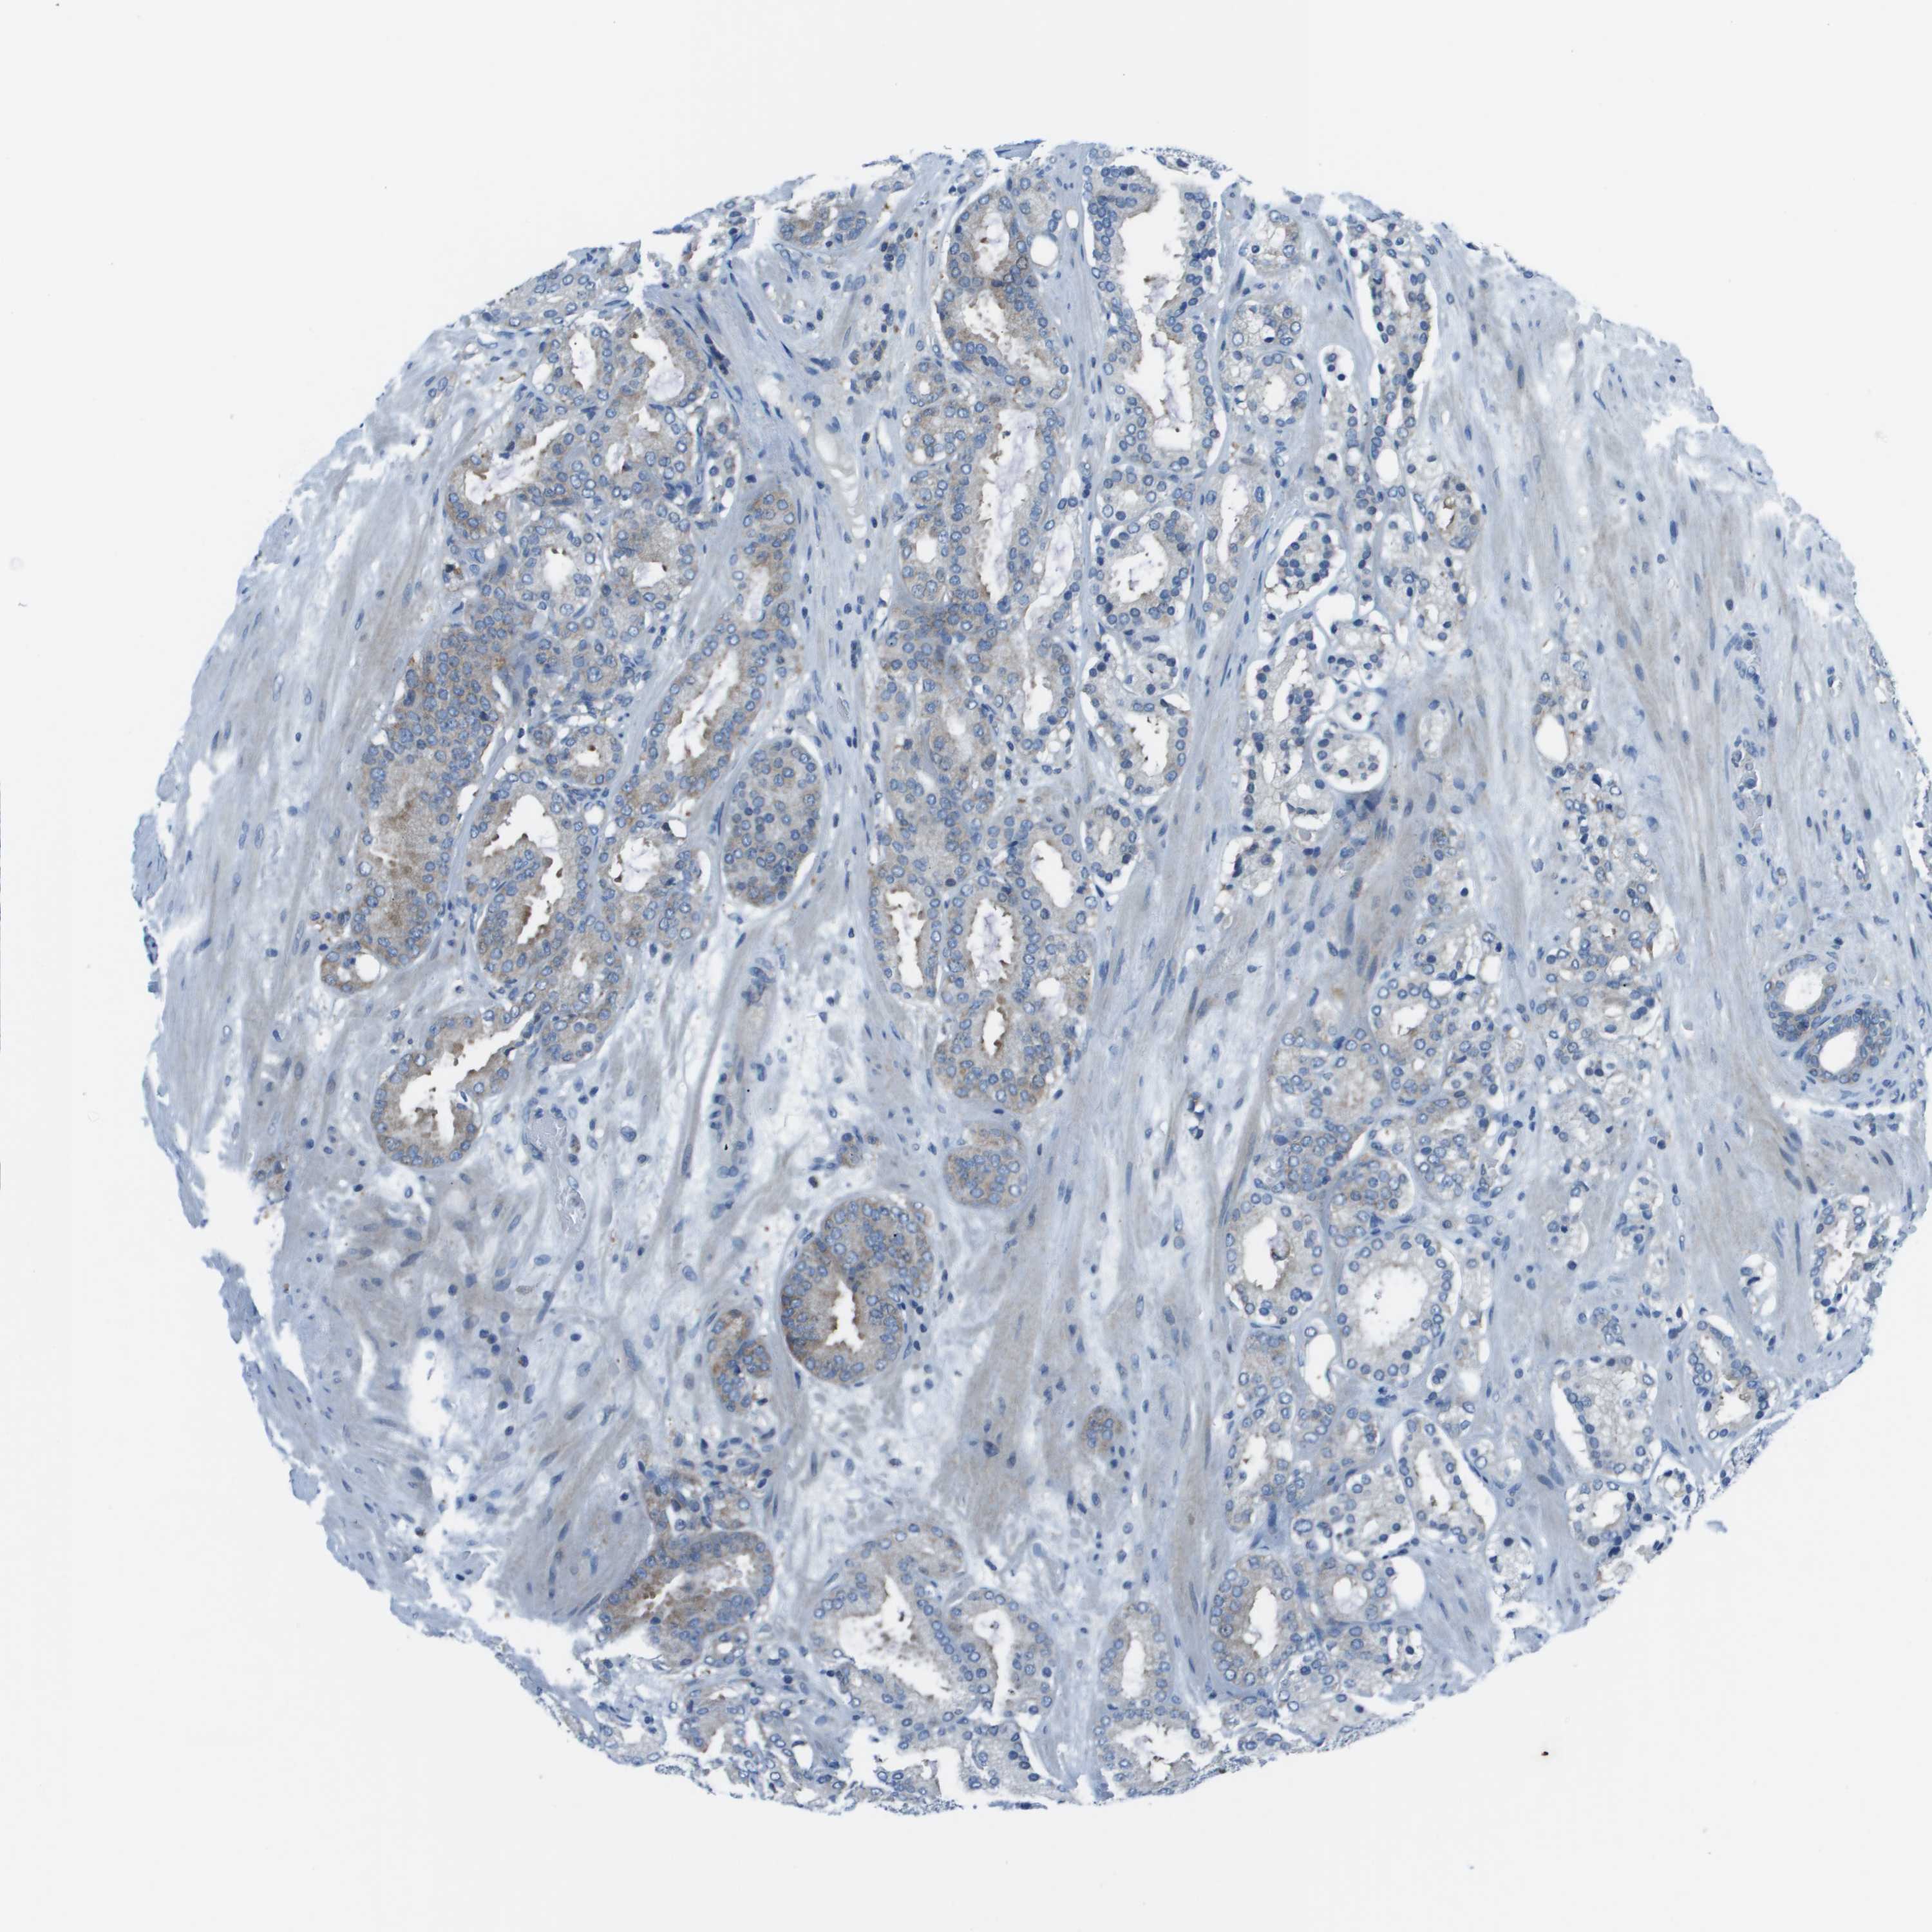

PROSTATE CANCER - Protein expressioni

A mouse-over function shows sample information and annotation data. Click on an image to view it in a full screen mode. Samples can be filtered based on level of antibody staining by selecting one or several of the following categories: high, medium, low and not detected. The assay and annotation is described here.

Note that samples used for immunohistochemistry by the Human Protein Atlas do not correspond to samples in the TCGA dataset.

Antibody stainingi

Antibody staining in the annotated cell types in the current human tissue is reported as not detected, low, medium, or high, based on conventional immunohistochemistry profiling in selected tissues. This score is based on the combination of the staining intensity and fraction of stained cells.

Each image is clickable and will lead to virtual microscopy that enables deeper exploration of all samples and also displays staining intensity scores, fraction scores and subcellular localization as well as patient and tissue information for each sample.

Antibody HPA039291

Antibody HPA044062

Antibody CAB017448

Staining

High

Medium

Low

Not detected

Intensity

Strong

Moderate

Weak

Negative

Quantity

>75%

75%-25%

<25%

None

Location

Nuclear

Cytoplasmic/membranous

Cytoplasmic/membranous,nuclear

Adenocarcinoma, High grade

Adenocarcinoma, Low grade